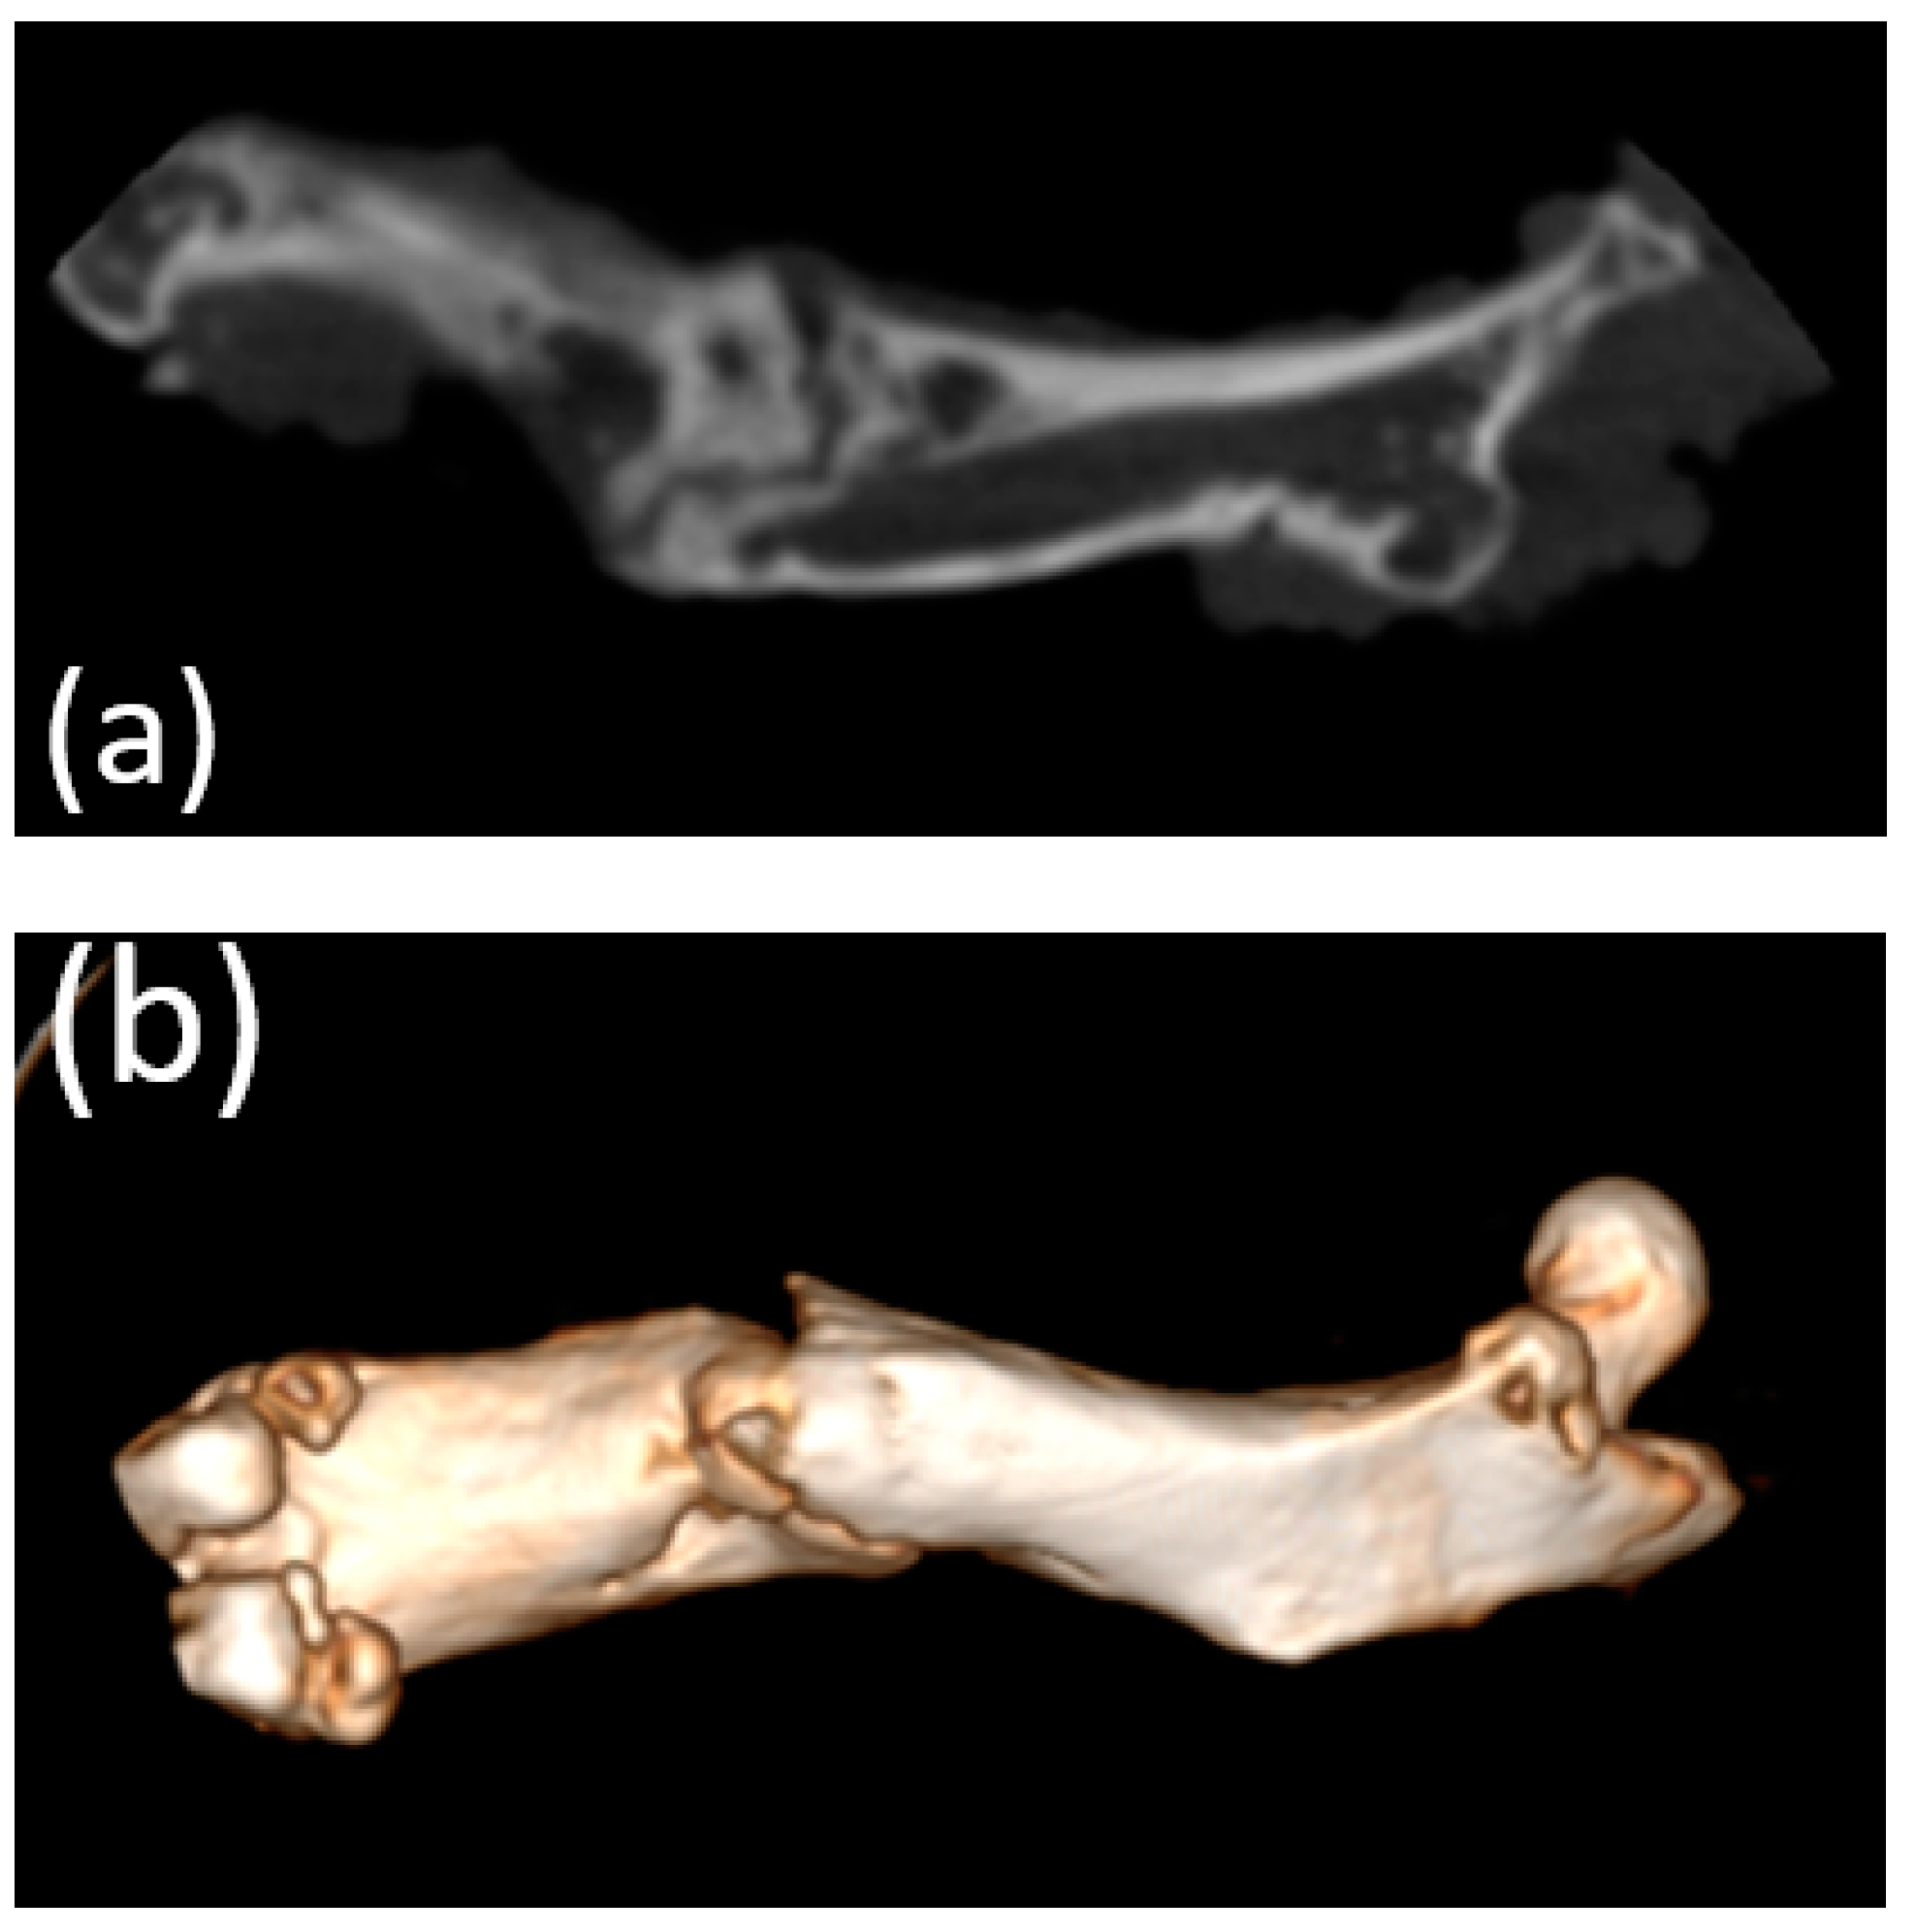

Micro-CT visualized increased density on the non-resorbed implant after 1 month (Figure 11a,b) in comparison with a slight decrease in the average density of implants after 3 months (Figure 12a,b)According to the micro-CT images 6 months after the operation, the holes formed for the implants were visualized, though the implants themselves were not visualized (Figure 13a,b). The resorption rates of the implants are shown in Table 1.

Figure 13. (a,b) Image of the femur of an animal 6 months after implantation (obtained using micro-CT). Only the holes for the implant placement were visualized; presumably, the implants had been completely resorbed.

The biodegradation of the implants in vivo was assessed using micro-CT. All implants studied were in direct contact with the surrounding bone and did not show any signs of any adverse reactions. The micro-CT results showed a slight decrease in implant density compared with a non-corroded implant 1 month after implantation. Micro-CT did not reveal the shape of the implant 3 months after implantation. In particular, this study showed that nearly 50% of the implant had degraded after 3 months, and complete bioresorption occurred after 6 months, which was also confirmed by the SEM and EDX analyses. The bone formation around the implants was a very good sign of osseointegration. We can conclude that the post-implantation histological bone formation assessed by micro-CT demonstrated osseointegration and, hence, good biocompatibility with the surrounding bone tissue.